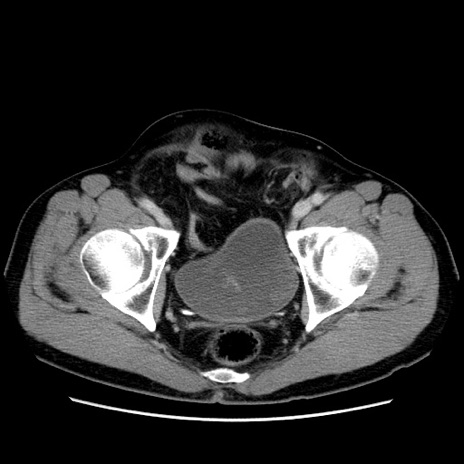

症例34(横断像)

【主訴】右鼠径部膨隆

【現病歴】1年程前より右鼠径部膨隆あり。自己にて還納可能だったため放置していた。3時間前より右鼠径部の脱出を認め、還納困難となり受診。

【身体所見】右鼠径部に小児頭大の膨隆あり。弾性硬であり、用手還納は困難。左鼠径部にも膨隆を認める。脱出はなし。

【データ】WBC 15500、CRP 測定なし